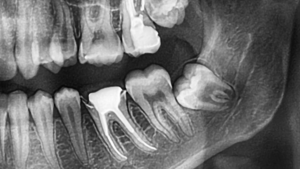

Managing Impacted Wisdom Teeth

Impacted wisdom teeth require additional steps because they are partially or fully trapped beneath the gums or bone, which makes removal more complex. This may involve removing a small portion of bone to fully access the tooth and ensure it can be extracted safely. The approach is carefully planned based on imaging to minimize disruption to surrounding tissue.

Moreover, managing impacted teeth properly helps prevent complications such as infection, damage to nearby teeth, or prolonged discomfort. Each case is handled individually based on the position and development of the tooth. This personalized approach helps improve outcomes and supports a more controlled healing process. Attention to detail during this stage is critical for long-term success.